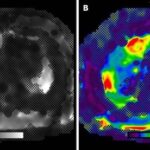

Elastografía

La elastografía es un método de imagen para cuantificar las propiedades mecánicas, en particular la rigidez, para evaluar los cambios cirróticos fibróticos focales (Anexo 14). Se puede cuantificar tanto la resonancia magnética como la ecografía, junto con un dispositivo que genera vibraciones de baja frecuencia (es decir, ondas transversales) y propagación de ondas, para calcular los niveles de rigidez en un área focal de interés. Introducidos por primera vez con la ecografía, existen múltiples métodos de elastografía que incluyen la elastografía transitoria, la onda transversal puntual, la onda transversal bidimensional y la elastografía cuasiestática. La elastografía por ecografía ha demostrado proporcionar una sensibilidad y especificidad satisfactorias para identificar los estadios histológicos de la fibrosis grave (sensibilidad: 81,9 %, especificidad: 84,7 %) y la cirrosis (sensibilidad: 84,8 %, especificidad 87,5 %). La elastografía por resonancia magnética también puede ayudar a diferenciar las lesiones hepáticas focales. Por ejemplo, se ha informado que los tumores malignos tienen mayores niveles de rigidez en relación con las lesiones benignas, las regiones fibróticas focales y el parénquima hepático normal.(23)